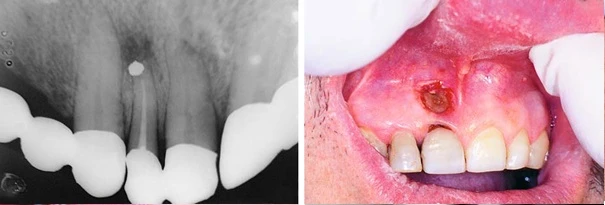

Phim X quang mô tả xoang trám không được chuẩn bị tốt chất trám ngược bị bong. Bên cạnh là hình ảnh không thể tái sinh xương, lộ chóp sau phẫu thuật do hở vết mổ.